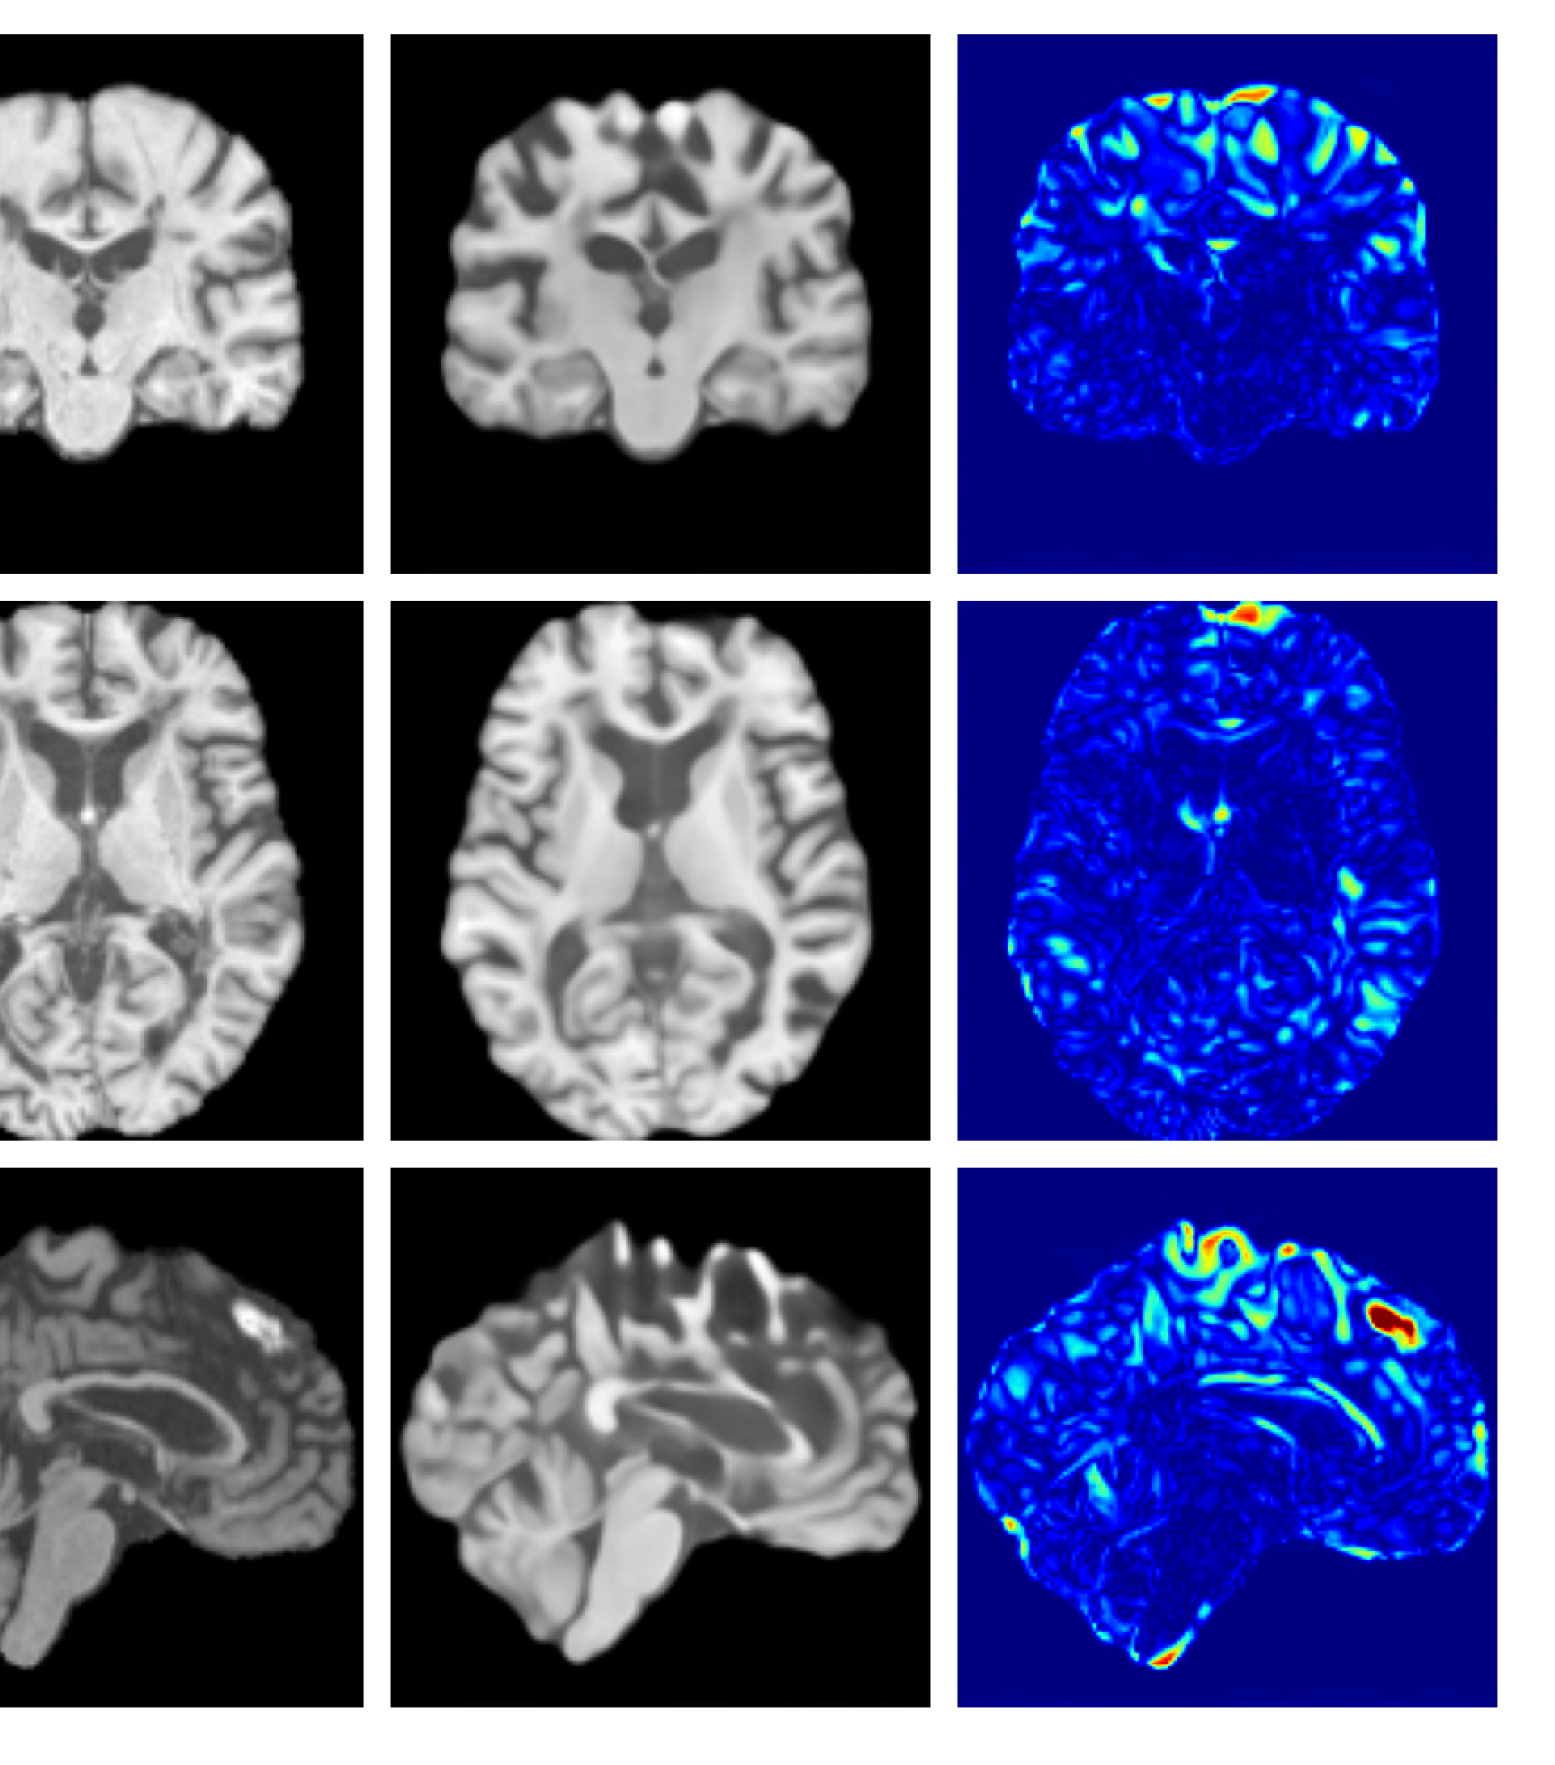

Figure 3: Example reconstructions and anomaly maps for a sample from the disease cohort of the UKBB dataset. Lesion and WMH are indicated in the original image by the red and yellow boxes respectively.

Figures 3 and 4, show example reconstructions and abnormality maps for a sample from the UKBB and UoTH datasets, respectively. Enlarged figures and additional example qualitative results for the ADNI dataset are available in the Supplementary. In Figure 3 we see that whilst all models are able to detect the lesion visible in the sagittal slice, the VAE, cVAE, LDM and LDM (TavgT_{avg}) produce very smooth outputs or lose defining characteristics and thus exhibit more false positives in healthy tissue. THOR and CADD provide the best results, with CADD better detecting white matter hypointensities (WMH). However, neither method fully inpaints all WMH, potentially due to presence of WMH in the healthy training set.